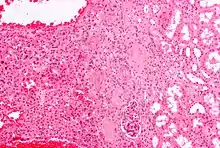

- Micrograph of a renal oncocytoma. H&E stain.

An oncocytoma is a tumor made up of oncocytes, epithelial cells characterized by an excessive amount of mitochondria, resulting in an abundant acidophilic, granular cytoplasm.[1][2] The cells and the tumor that they compose are often benign but sometimes may be premalignant or malignant.

An oncocytoma is an epithelial tumor composed of oncocytes, large eosinophilic cells having small, round, benign-appearing nuclei with large nucleoli.